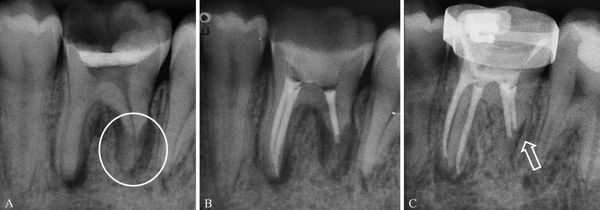

- Резорбция корня — патологическое рассасывание корней из-за наличия очага хронического воспаления (определяется только рентгенологически).

При первичном визуальном осмотре специалист определяет характер травмы без труда, так как признаки вывиха проявляются достаточно ярко. Но для более детального изучения характера и формы патологии (для оценки состояния челюсти, соседних зубов и иннервации в области повреждённого зуба) стоматолог назначает рентгенологическое исследование: ортопантомографию (ОПТГ) или компьютерную томографию челюсти . Это поможет дифференцировать вывих от иных форм травмы зуба (ушиба и перелома), кроме этого оценить структуру костной ткани, окружающей зуб на предмет трещин и перелома.

После неполного вывиха не исключена внешняя резорбция (рассасывание) корня, которая не прогрессирует. При этом выраженность процесса резорбции определяется степенью смещения корня зуба при вывихе: чем больше смещение, тем большая поверхность корня может подвергнуться разрушению.

- После реплантации необходимо в течение от одного до двенадцати месяцев проводить рентгенологический контроль. Это позволяет судить о состоянии корня зуба, периодонта и кости.

Репозицию вколоченной травмы с фиксацией на 4-6 недель нужно проводить не позже трёх суток после вывиха. Эта манипуляция сопровождается потерей краевого участка альвеолы и последующей резорбцией корня зуба. Полноценное лечение корневых каналов зуба производится после укрепления зуба в лунке [6] .